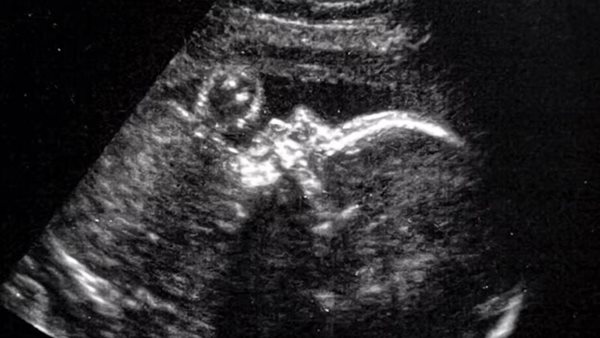

الفريق الطبي مكوّن من عشرة أفراد في مستشفى بوسطن للأطفال ومستشفى ماساتشوستس العام بأمريكا، والإجراء الدقيق تضمن قطع رحم الأم وجمجمة الجنين، ثم إجراء العملية على الدماغ النامي، من خلال استخدام الموجات فوق الصوتية لتحديد الشريان وتوجيه الجراحة.

حدد الأطباء التشوه في الأم باستخدام الرنين المغناطيسي، وحددوا الجيوب الأنفية شديدة الاتساع، والوريد المنحني في الدماغ الذي يستنزف الشريان، وهو ما أكد للجراحين أن هناك فرصة بنسبة 99٪ لحدوث التشوه.